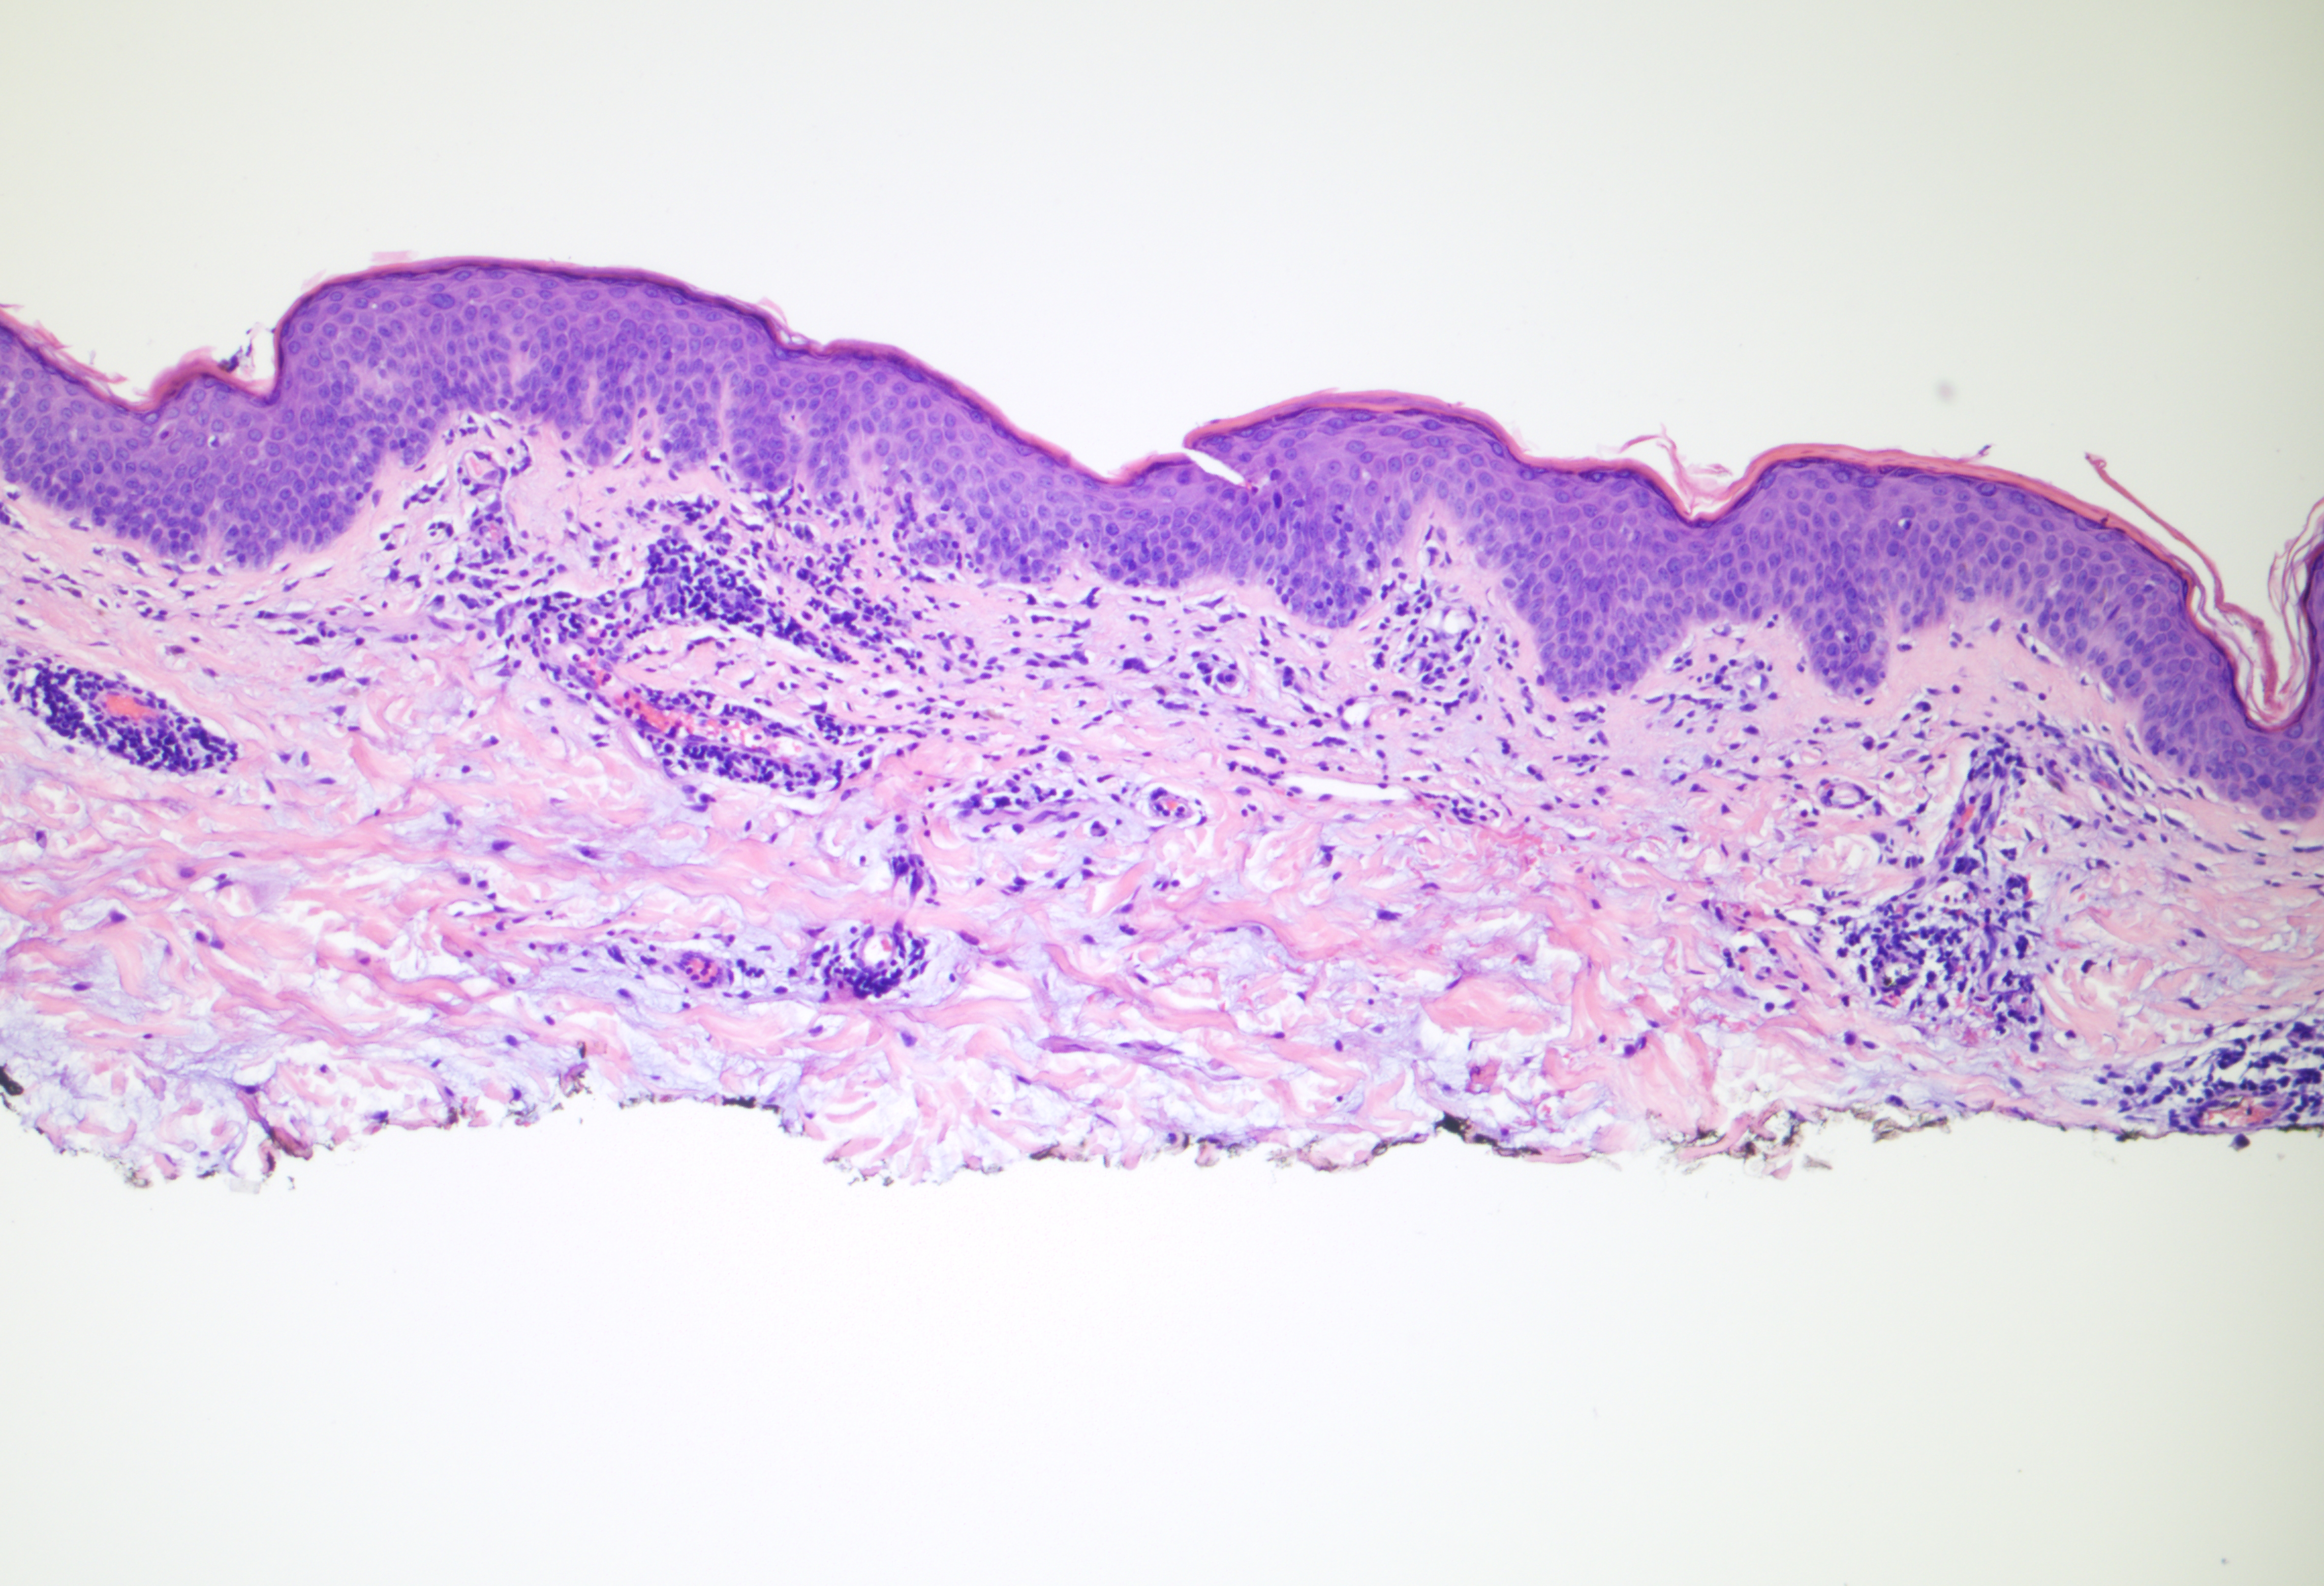

47-year-old Caucasian woman with erythematous macules, patches, and keratotic plaques on neck and upper chest